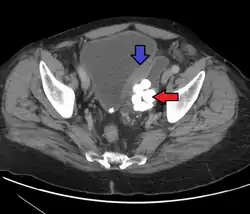

Transitional cell carcinoma is a type of cancer that arises from the transitional epithelium, a tissue lining the inner surface of these hollow organs.[1] It typically occurs in the urothelium of the urinary system; in that case, it is also called urothelial carcinoma. It is the most common type of bladder cancer and cancer of the ureter, urethra, and urachus. Symptoms of urothelial carcinoma in the bladder include hematuria (blood in the urine). Diagnosis includes urine analysis and imaging of the urinary tract (cystoscopy).

Transitional cell carcinomas are often multifocal, with 30–40% of patients having more than one tumor at diagnosis. The pattern of growth of transitional cell carcinomas can be papillary, sessile, or carcinoma in situ. The most common site of transitional cell carcinoma metastasis outside the pelvis is bone (35%); of these, 40 percent are in the spine.[10]